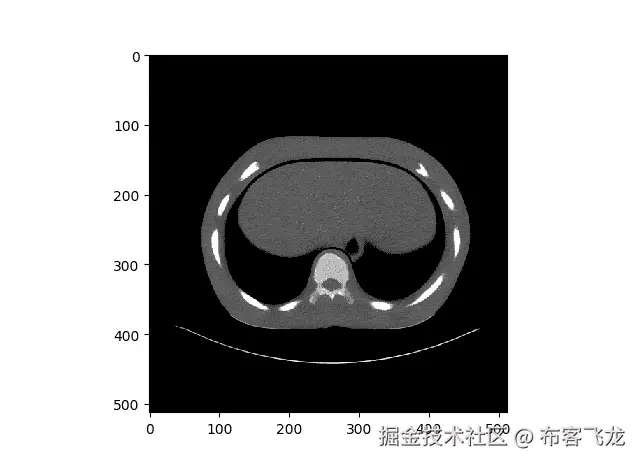

如上文中所见,作者(陈虎)将一幅图像分割成独立的图像块。现在,我们不打算使用与本文中完全相同数量的补丁,而是将我们的训练和测试映像分成几个补丁。下面可以看到一个训练图像。

第一行图像 →原始图像和分割补丁 第二行图像 →添加噪声图像和分割补丁

因此,原始图像的尺寸为(512512 ),我们将把图像分成 4 个小块。更具体地说,每个图像块将具有(256256)维。记住这一点,下面是其他训练和测试数据的例子。(此外,我忘了拍摄分割后的原始图像,所以这就是为什么你看不到它们的原因。)